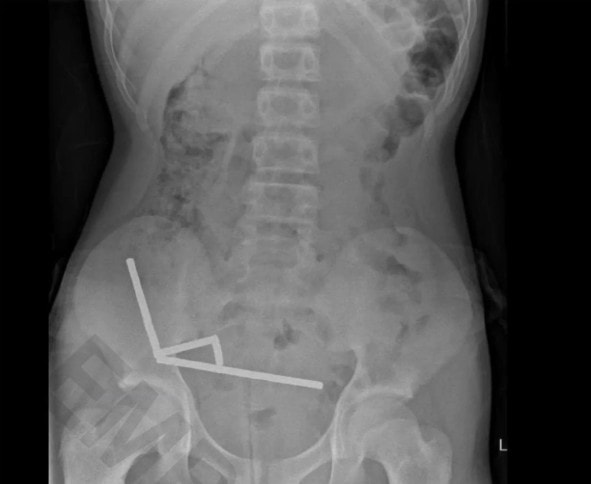

Ca phẫu thuật diễn ra tại Bệnh viện Tauranga, sau khi cậu bé nhập viện vì đau bụng dữ dội và thừa nhận đã nuốt số nam châm này một tuần trước, theo thông tin từ Tạp chí Y khoa New Zealand hôm 23/10. Bác sĩ phẫu thuật Nicola Davis cho biết các viên nam châm, được cho là mua từ sàn thương mại điện tử Temu, đã hút nhau qua các thành ruột, gây áp lực lớn dẫn đến thủng ruột.

"Chúng tôi buộc phải loại bỏ toàn bộ số nam châm và cắt đi một phần ruột bị tổn thương", bác sĩ Davis nói. Ca mổ đã thành công, bệnh nhân được xuất viện sau 8 ngày điều trị.